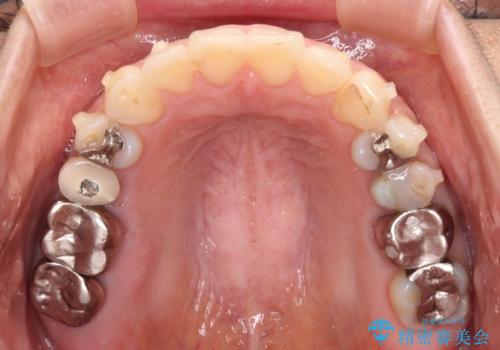

後戻りは軽微であったため、インビザライン・ライトにて歯列を整えました。

矯正治療後には、左下奥歯の症状がないことを確認し、セラミッククラウンにて補綴治療を行うこととしました。